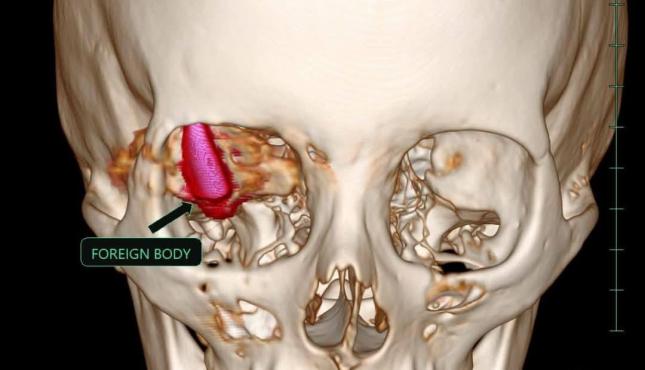

وكانت الشابة الفلسطينية قد تعرضت لإصابة بالغة نتيجة إصابتها بطلقة نارية اخترقت جمجمتها واستقرت خلف العين في منطقة حساسة، حيث تم إطلاقها من طائرة "كواد كابتر" خلال النزوح الذي تعرضت له في منطقة النصيرات.

ووصف الأطباء المصريون، العملية بأنها "بالغة التعقيد، حيث كان الطلق الناري قد استقر في منطقة حساسة داخل الجمجمة، مما كان يشكل تهديداً كبيراً على حياة المريضة".